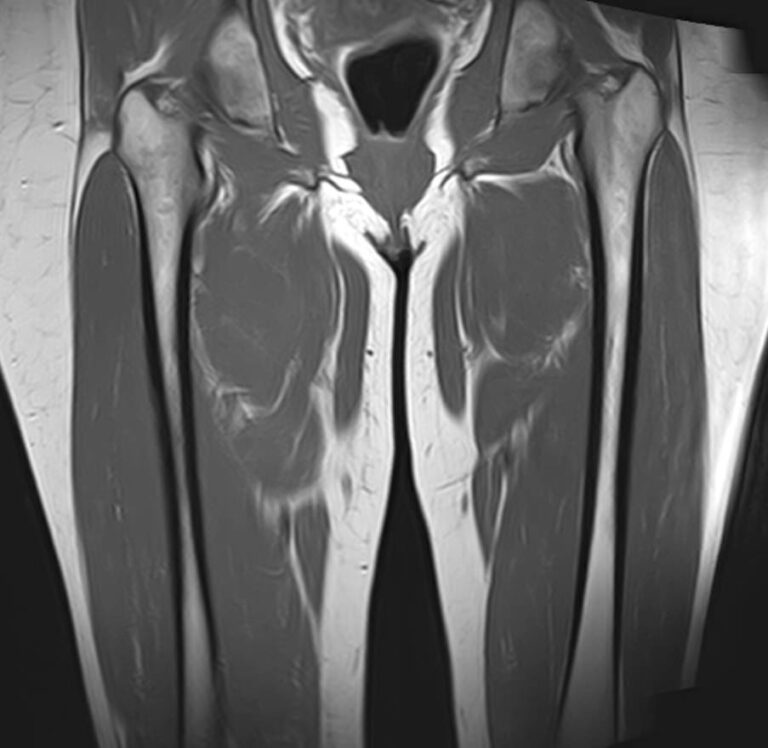

Магнитно-резонансная томография применяется для обследования мягких тканей верхних и нижних конечностей, включая кожу, подкожно-жировую клетчатку, мышцы, фасции, межфасциальные пространства, сухожилия, связки, сосудистую систему, лимфоузлы и лимфатические протоки, нервные волокна, надкостницу и костный мозг.

Кроме того, имеет значение показатель индукции магнитного поля томографа. Наша клиника оснащена современным высокопольным томографом последнего поколения TOSHIBA VANTAGE TITAN 1,5 Тесла. Высокая индукция магнитного поля обеспечивает повышенную четкость изображений при обследовании мягких тканей конечностей. За счет послойного сканирования в различных плоскостях с шагом от 1 мм и последующего преобразования данных в объемные изображения томограф обеспечивает выявление мельчайших изменений в тканях. Это позволяет проводить диагностику различных заболеваний на самых ранних стадиях.

- Доброкачественные опухоли конечностей.

- Злокачественные новообразования (как первичные опухоли конечности, так и метастатические поражения из других очагов).

- Травматические повреждения (растяжения, разрывы мышц, связок, сухожилий)